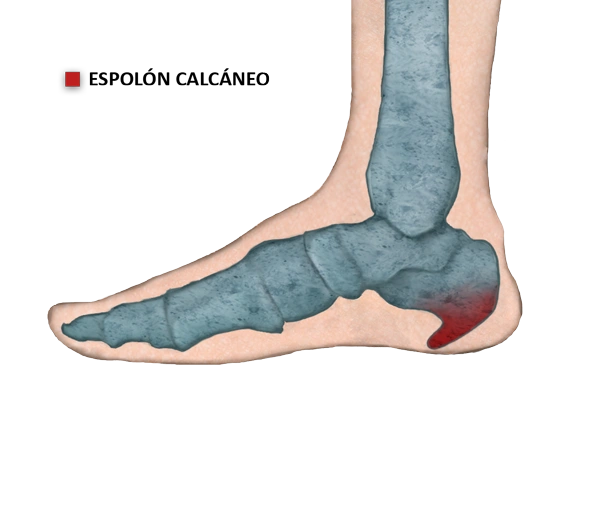

El espolón calcáneo, es una una calcificación que produce una protubernacia ósea puntiaguda sobre el calcáneo, la parte inferior del hueso del talón, como consecuencia de estiramientos excesivos y continuados de la fascia plantar, una banda de tejido conjuntivo que recubre los músculos de la zona.

Diagnóstico El espolón se puede diagnosticar con una radiografía lateral del calcáneo, donde se reconoce una protuberancia orientada hacia los dedos y que puede variar entre 1 y 5 mm.